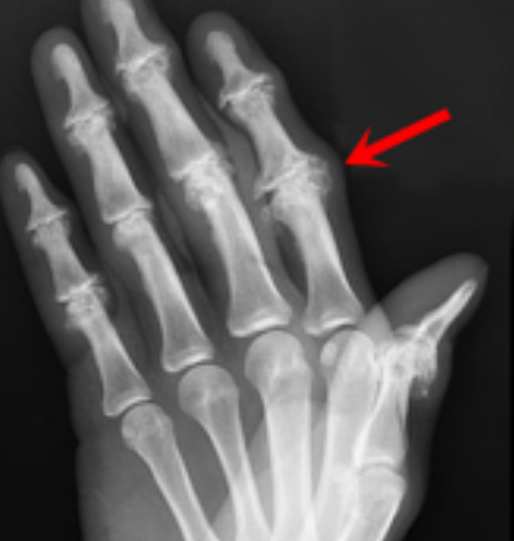

Name the feature the arrow is pointing at.

Bouchard’s nodes